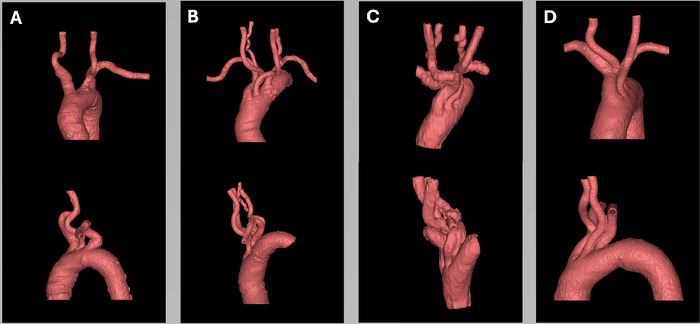

Methods: To better understand the challenges of tortuous anatomy, we fabricated 3D-printed models of the aortic arch and major branch vessels based on the imaging of 4 patients.

Results: These patient-specific models were realistic representations of the intricate vascular pathways and provided enhanced visualization of the complex vascular structures. The measured diameters of the 3D-fabricated models closely matched the values reported in the literature, confirming the physical accuracy of the models. Creating an individual anatomic model required an average of 4 hours of digital processing and 13.71 hours of 3D printing, with a materials cost of approximately $17.31.

Conclusion: 3D-printed patient-specific models used for neurointerventional training and preprocedural planning are a valuable tool for managing complex cerebrovascular anatomy. The advanced visualization provided by these models may enhance preparedness and potentially improve ischemic stroke treatment outcomes.